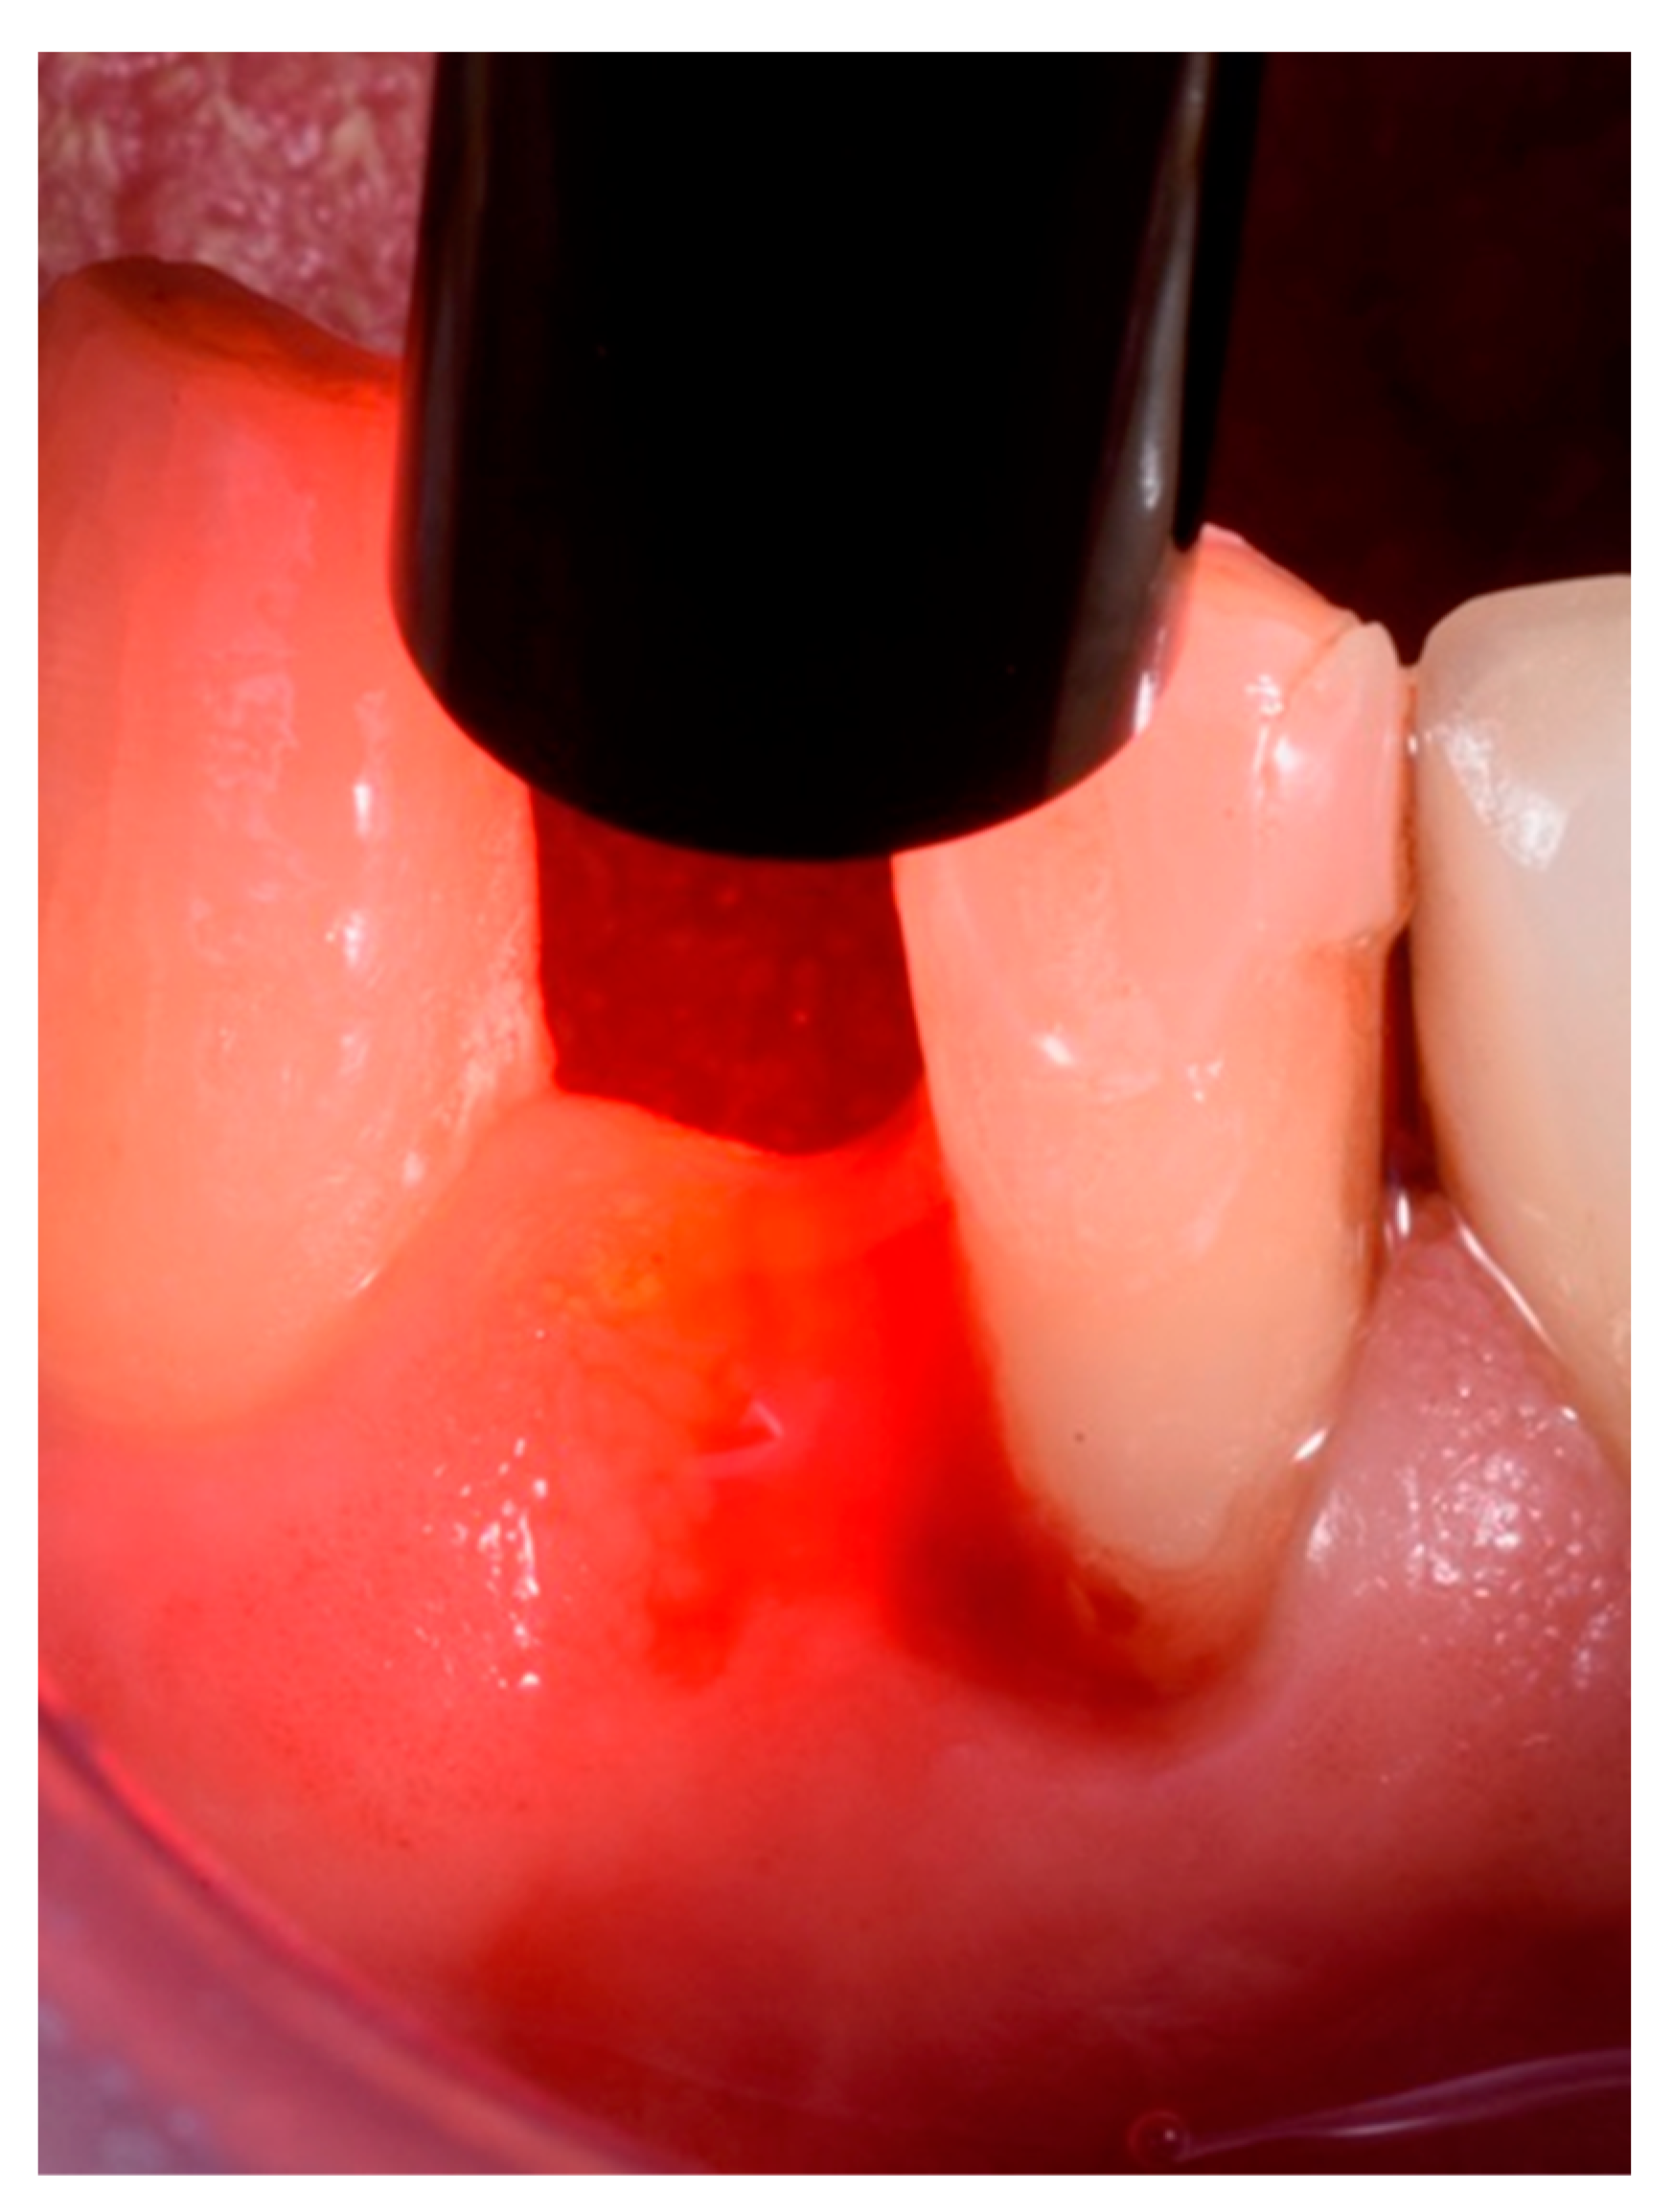

4.1. Clinical Procedure